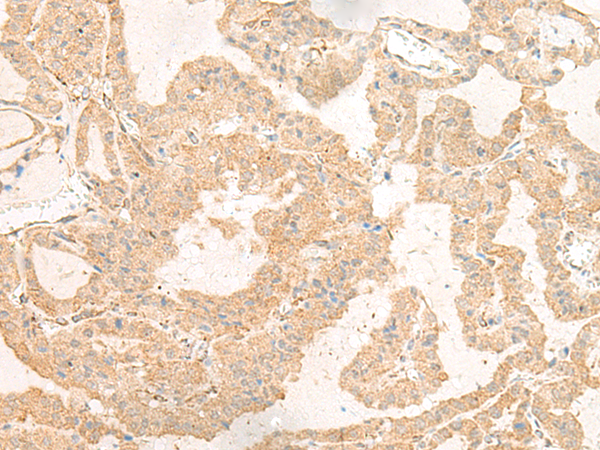

ELISA, IHC |

IHC positive control: |

Human thyroid cancer and Human esophagus cancer |

IHC Recommend dilution: |

40-200 |